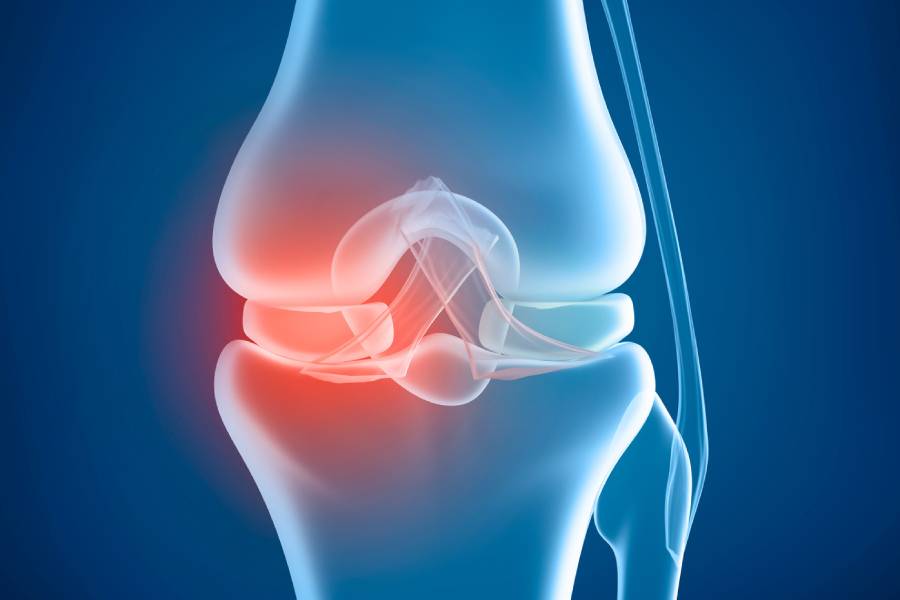

Joint Replacement Surgery, also known as Arthroplasty, is a medical procedure in which a damaged or worn-out joint is replaced with an artificial implant (prosthesis). These implants replicate the natural movement of a healthy joint, reducing pain and restoring mobility.

In simple terms, joint replacement means removing damaged cartilage and bone from a diseased joint and substituting it with a metal, plastic, or ceramic implant designed to function like a natural joint. It’s one of the most successful orthopaedic procedures today, improving millions of lives worldwide. Patients who undergo Total Joint Replacement Surgery typically regain strength, flexibility, and the ability to perform everyday activities without pain. You can also learn more about the joint replacement procedure through a joint replacement video demonstration, often shared during consultations at OrthoPatna, to help patients understand what to expect before and after surgery.